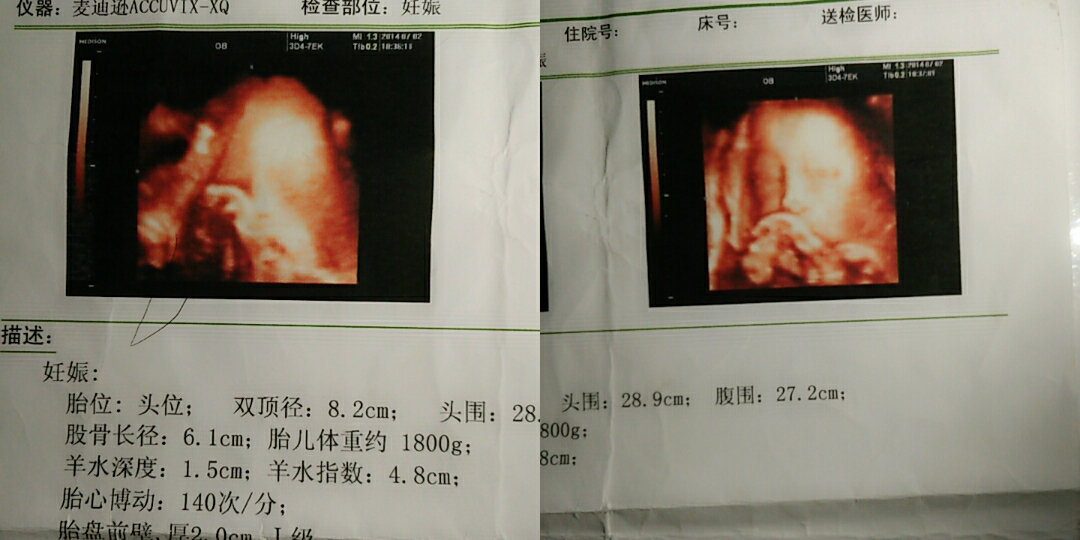

后来做了四维宝宝很健康只是肚子比平常孕妇小很多胎儿也小两周,原因都是我吃不习惯这边的东西吧,(婆婆在乡下没跟我住的一块)加上孕早期感觉特别疲惫有时候睡觉一睡就睡到了中午才起来吃饭,(这是一个当妈非常不及格的行为)上张四维图哦~

这是我女儿的四维图,感觉还蛮乖的哈😄